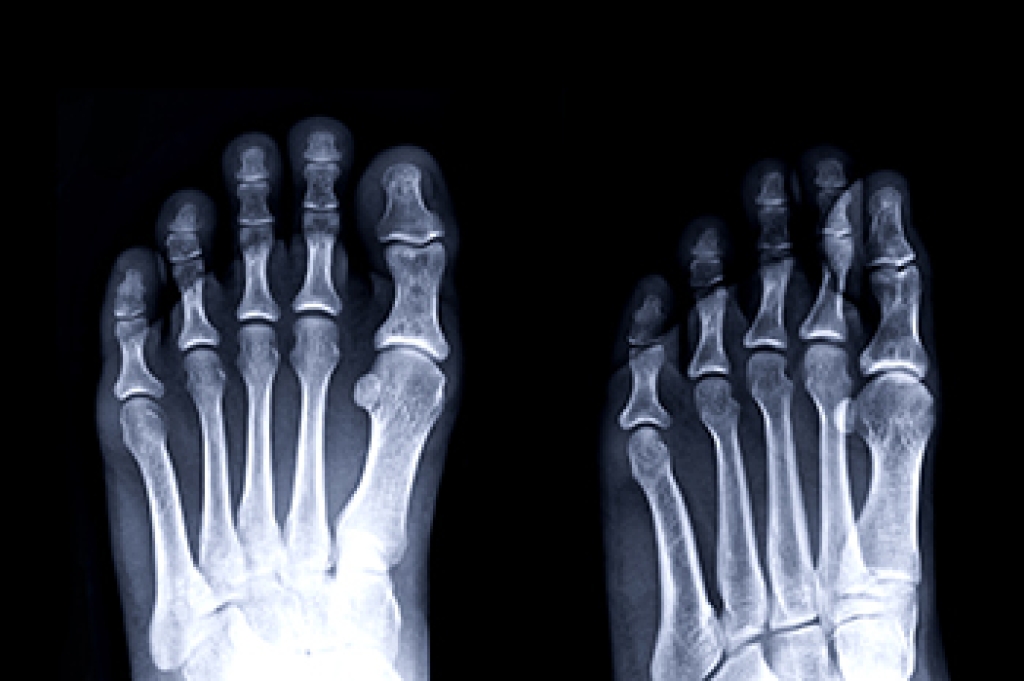

A common concern when it comes to foot health, having properly fitted shoes can help prevent injuries to the foot. Out feet affect our posture and gait, which in turn affects the biomechanics and overall bodily structure. With 33 joints, 26 bones, and over 100 ligaments, the potential for serious injury is much greater than one realizes. Although the feet cease growth in adulthood, they still change shape as they mature. Here are some factors to consider when it comes to investing in proper fitting shoes: